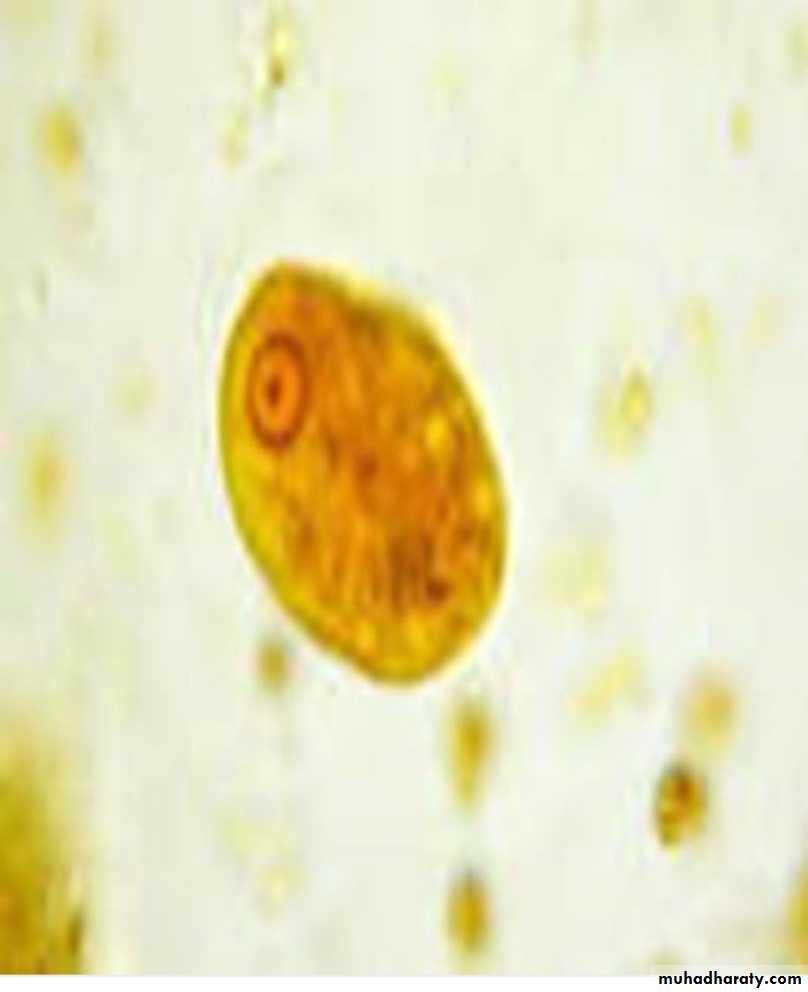

Two stages :-Trophozoite

Cyst